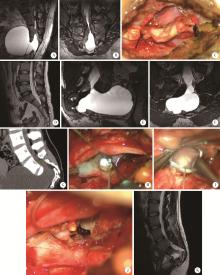

表2

5例骶管囊肿合并骶前囊肿患者的一般资料"

Items Gender Maximum diameter of cyst/cm

Sacral canal Presacral

With nerve root fiber

Case 1 Male 4.4 6.2

Case 2 Female 5.5 8.6

Without nerve root fiber

Case 1 Male 4.0 8.0

Case 2 Female 3.6 14.0

Case 3 Female 2.5 1.0

图3

骶管囊肿合并骶前囊肿的典型病例"